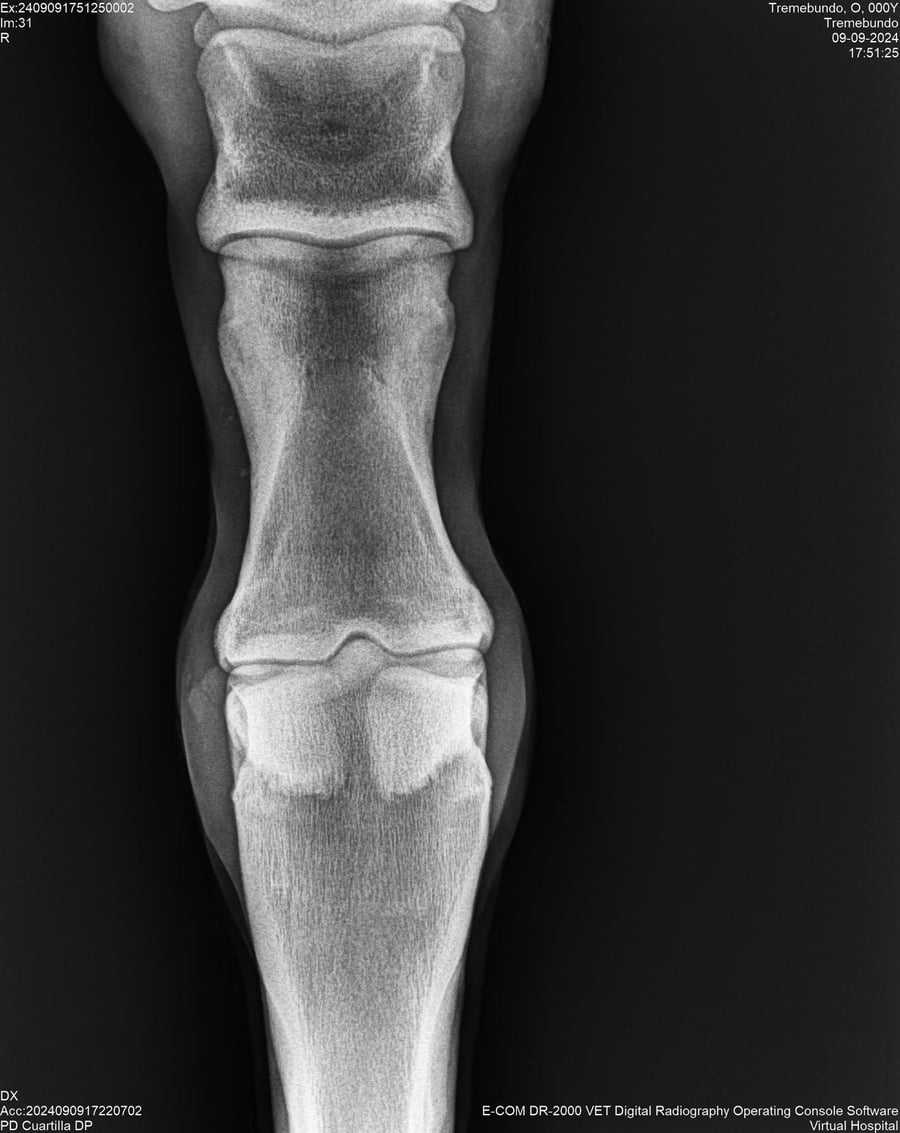

LOTE 37, TREMEBUNDO

Ficha del Lote

Identificador: #291140-

Generacion 2022